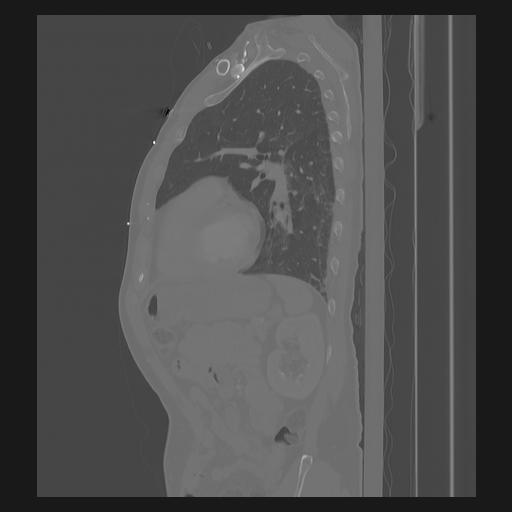

33 PULMON,CE,Sagittal,3.000,PULMON,Sagittal,